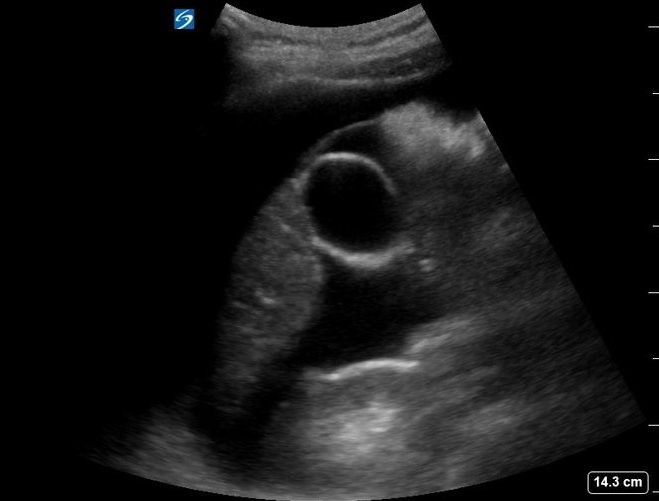

At the same time of the initial emergency physician evaluation, an ultrasound examination using a curvilinear transducer of the right upper quadrant revealed a large amount of intraperitoneal fluid (Figure 1, Video 1). The visualized uterine cavity was empty with mixed echogenicity surrounding the uterus. A bulging abnormality was noted in the anterior myometrium in the lower uterine segment, corresponding to the site of her prior Cesarean section (Figure 2). A gestational sac was visualized in the lower anterior uterine segment with a visible embryo and fetal heart movement. There was a thin amount of tissue between the sac and maternal bladder measuring 4.8 mm (Figure 3, Video 2).

Figure 1. Right upper quadrant ultrasound demonstrating large amount of free fluid.